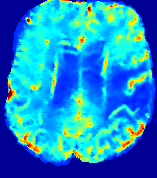

4.3.2 Diffusion Imaging via Advection-Diffusion

Slice #1Slice #2Slice #3Slice #4Slice #5Slice #6Dgtsuperscript𝐷gtD^{\text{gt}}Refer to captionRefer to captionRefer to captionRefer to captionRefer to captionRefer to captionDestsuperscript𝐷estD^{\text{est}}Refer to captionRefer to captionRefer to captionRefer to captionRefer to captionRefer to captionRefer to caption0.300.300.300.240.240.240.180.180.180.120.120.120.060.060.060.000.000.00(mm2/s)𝑚superscript𝑚2𝑠(mm^{2}/s)𝐕est𝟐subscriptnormsuperscript𝐕est2\|\bf{V}^{\text{est}}\|_{2}Refer to captionRefer to captionRefer to captionRefer to captionRefer to captionRefer to captionRefer to caption0.00300.00300.00300.00240.00240.00240.00180.00180.00180.00120.00120.00120.00060.00060.00060.00000.00000.0000(mm/s)𝑚𝑚𝑠(mm/s)

Figure 15: PIANO identifiability testing: diffusion imaging via advection-diffusion. Top row shows Dgtsuperscript𝐷gtD^{\text{gt}} used for simulating ground truth pure diffusion. Rows below show the estimated Destsuperscript𝐷estD^{\text{est}} and 𝐕est2subscriptnormsuperscript𝐕est2\|{\bf{V}}^{\text{est}}\|_{2} on corresponding slices. Note that the plotted value scale for 𝐕est2subscriptnormsuperscript𝐕est2\|{\bf{V}}^{\text{est}}\|_{2} is 0.01 of that for Dgtsuperscript𝐷gtD^{\text{gt}} and Destsuperscript𝐷estD^{\text{est}}.

Similarly, we test the behavior of PIANO when estimating both advection and diffusion from a pure diffusion-driven process. The goal is to determine if PIANO is able to recognize that there is only diffusion governing the given concentration time-series. We use the same ‘Diffusion Imaging’ data simulation of Sec. 4.2.1 as the concentration dataset, PIANO estimates both velocity 𝐕estsuperscript𝐕est{\bf{V}}^{\text{est}} and diffusivity Destsuperscript𝐷estD^{\text{est}}. Estimation results in Fig. 15 confirm PIANO’s identifiability again: the estimated 𝐕est2subscriptnormsuperscript𝐕est2\|{\bf{V}}^{\text{est}}\|_{2} is almost invisible compared to Destsuperscript𝐷estD^{\text{est}}, even plotted with a 1%percent11\% value range compared to that for Destsuperscript𝐷estD^{\text{est}}. On the other hand, Destsuperscript𝐷estD^{\text{est}} achieves comparable estimation performance as ‘Diffusion Imaging via Diffusion’ in which PIANO predicts Destsuperscript𝐷estD^{\text{est}} alone (shown in Fig. 13).